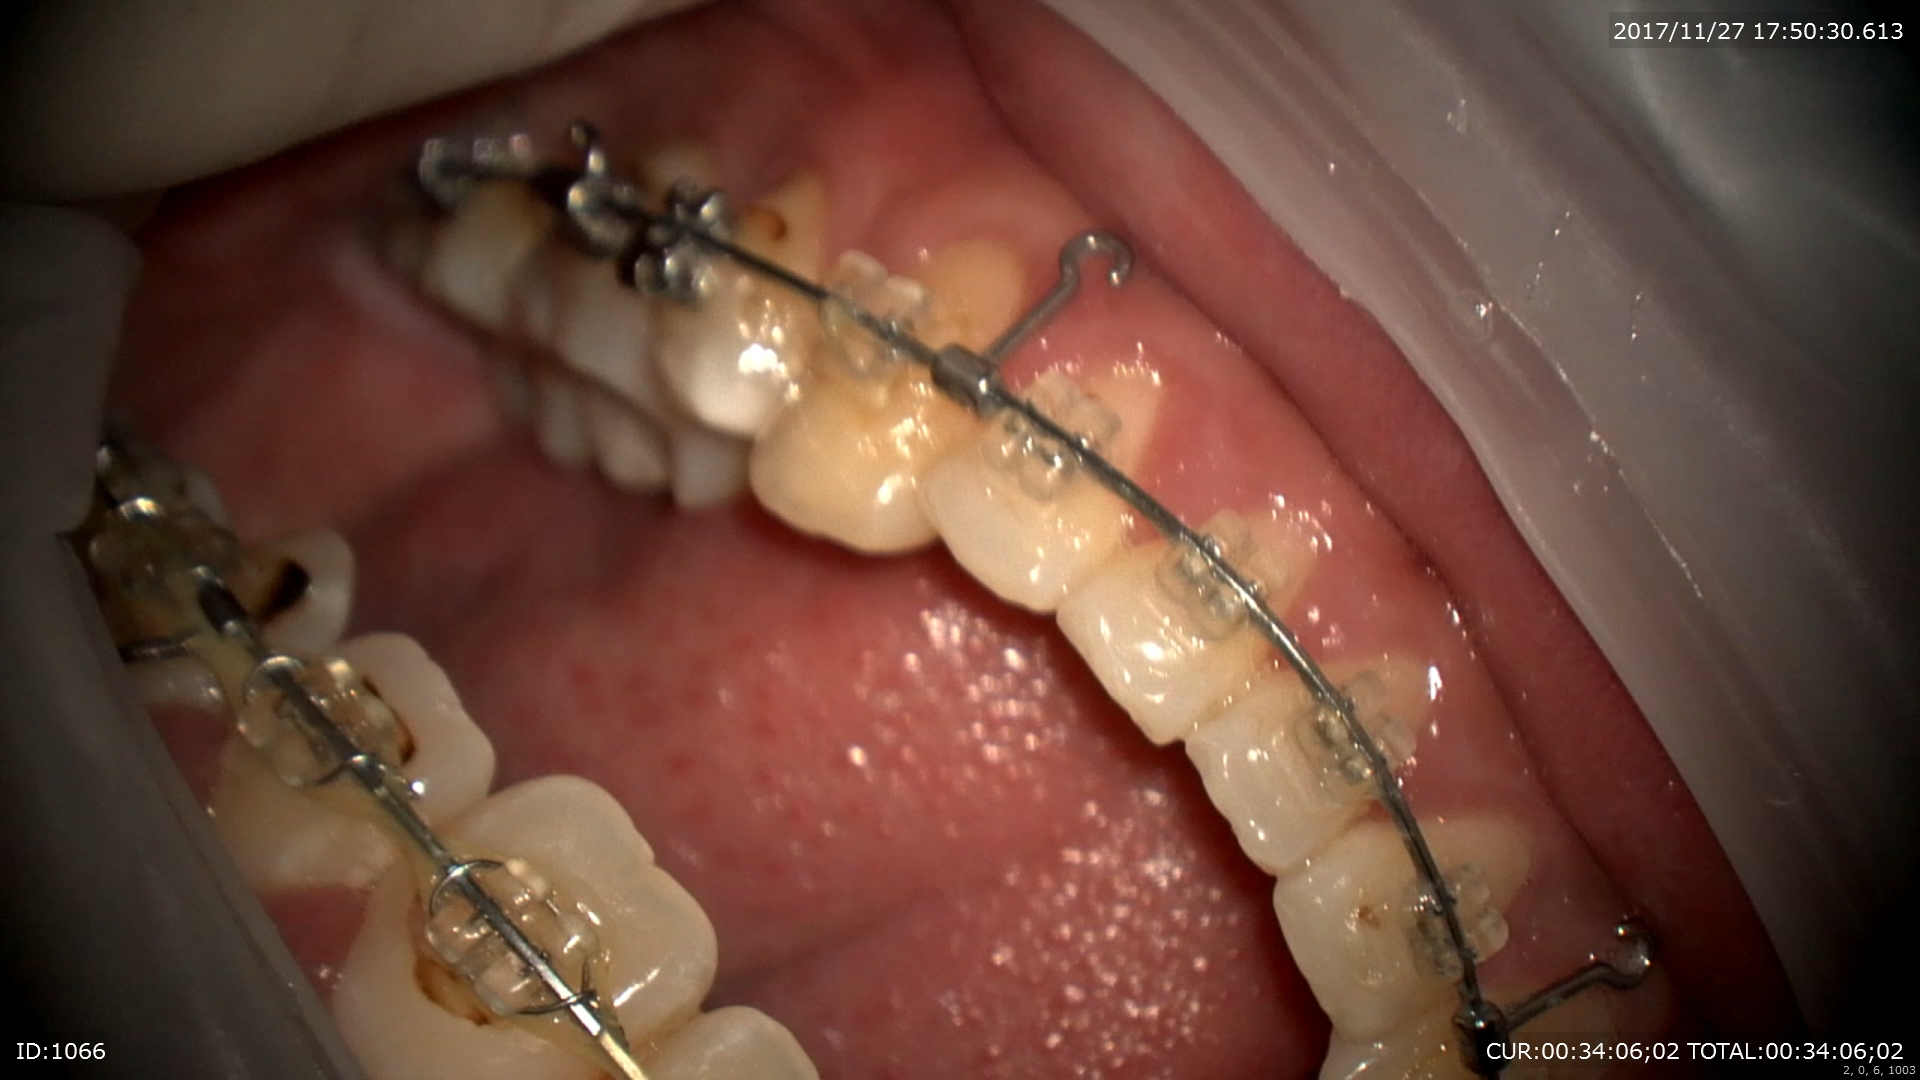

2ケース目は矯正治療

ブラケットを装着するときにもマイクロスコープ。正確につけます。

抜歯空隙のスペースを閉じる為

ワイヤーベンド マイクロスコープ下で針金を曲げトルクのチエック

治療の終盤になったのでオーダーメイドで歯の位置を変えていきます。

来月はスペースクローズが完了するはず。彼は矯正したことで顔が変わり喜んで頂けました。彼のお母さんも喜んでいます。かみ合わせや歯並びはお顔も良くします。

このように当院では精密な診断の元矯正治療を行っております。松戸、流山、八潮、三郷で矯正をお考えの方はBiVi歯科・矯正歯科まで。